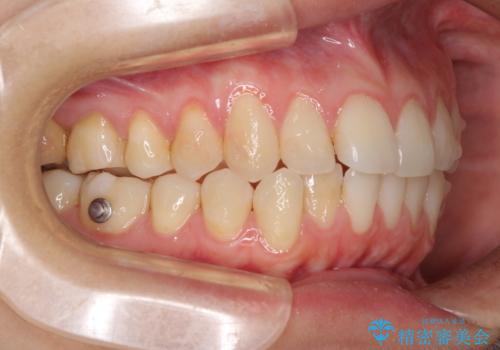

- 矯正装置

- インビザライン

- 上下前歯のデコボコを気にして来院された患者様です。

インビザラインによる上下歯列の側方拡大と後方移動、IPR(歯と歯の間を削る)にるスペースの獲得により歯列を整えることとしました。